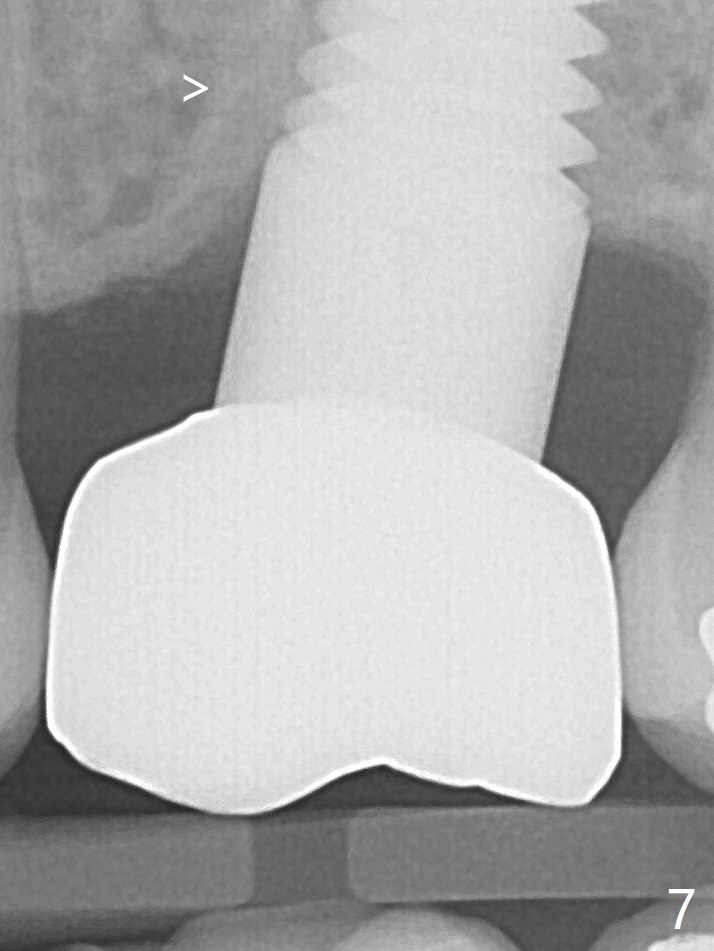

Prior to placement of 6x17 mm soft tissue level implant (Fig.1), the same size of tap is used. When the latter is removed, there is a small defect in the buccal wall of the osteotomy (mainly in the palatal socket) with the intact sinus membrane. There is no intraop or postop nasal hemorrhage. The patient returns for restoration 7 months postop; it appears that there is osteo-integration (Fig.2 with the mesial gap getting smaller (>)). The gingiva is healthy buccal (Fig.3: B) and palatal (Fig.4: P). The mesial gap is closed with formation of dense bone 4 years post cementation (Fig.7). Fig.5 is the preop PA of the patient, which shows that the palatal root (pink dashed line) is above the sinus floor and surrounded by the lamina dura. Fig.6 is a coronal section of the 2nd molar of another patient, which shows that the palatal root is 5-6 mm above the sinus floor. Upper Molar Immediate Implant Follow-Up Xin Wei, DDS, PhD, MS 1st edition 10/13/2013, last revision 05/18/2018